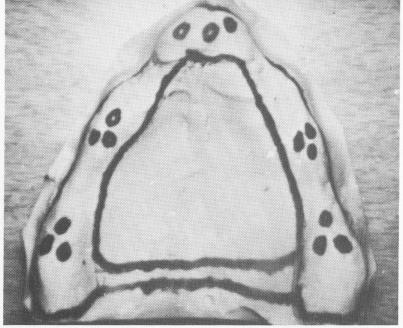

Fig. 10-224. An outline for the template was made directly on the master stone model. (From Linkow, L. I.: Maxillary endosseous implants, Dent. Concepts 10[1]:14-24, 1966.)

Fig. 10-227. The master stone model was poured from an elastic impression.